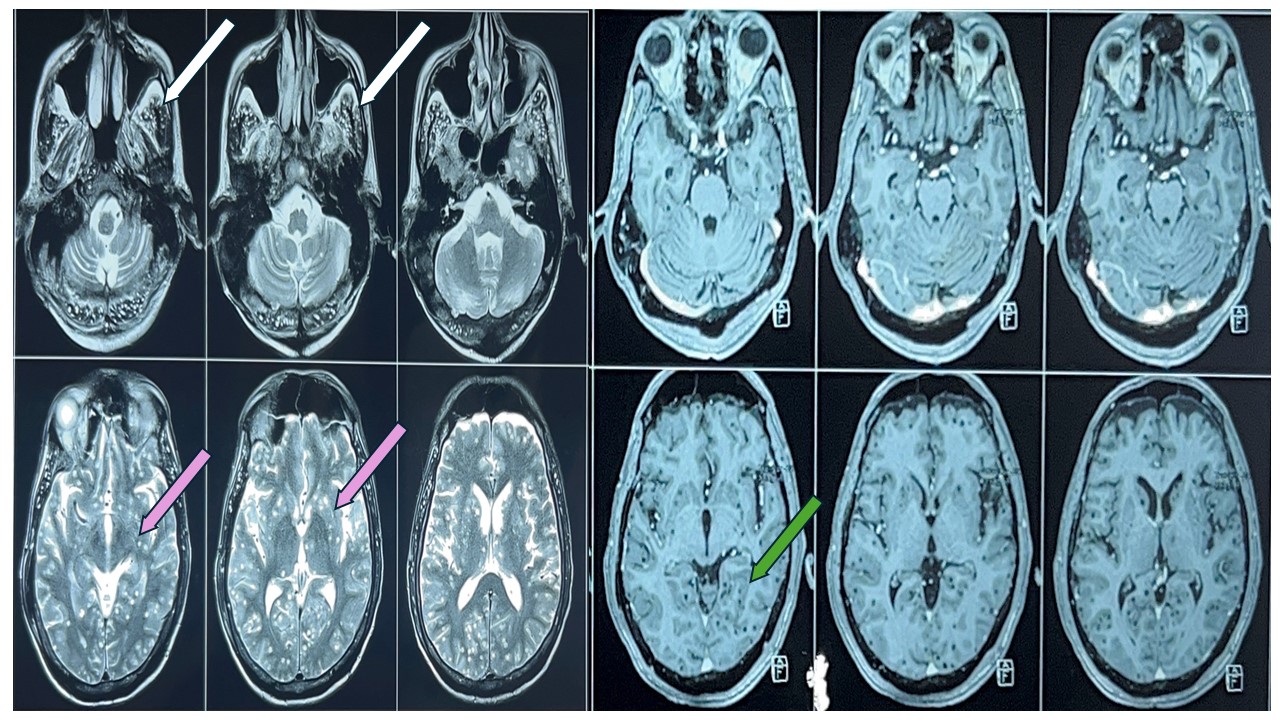

Given the asset restrictions in our setting, the patient went through a designated and stepwise workup. His complete blood count, renal, liver, and electrolytes were unremarkable. Serology for hepatitis B, C, and human immunodeficiency virus (HIV) were negative. The erythrocyte sedimentation rate was 35 mm/hr, and the C-reactive protein level was 1.2 mg/dL.His Vitamin B12, folate, and serum homocysteine levels were normal. Computed tomography scan of head was within normal limit. The electroencephalogram (EEG) revealed a slowed background rhythm without epileptiform discharges, which is indicative of moderate encephalopathy.Cerebrospinal fluid (CSF) showed a normal pressure of 10 cm of water with normal cells, protein, sugar, and no bacterial or fungal growth. CSF cartridge-based nucleic acid amplification test (CBNAAT), VDRL and viral panel reports came negative. Noncontract computed tomography (CT) head was within normal limit. Magnetic resonance imaging of the Brain (MRI) with contrast was done, which showed a starry sky appearance, suggesting multiple NCCs (Figure 1).

Figure 1 - Multiple T2 hyperintense lesions seen in bilateral cerebral and cerebellar hemispheres as depicted by white arrow (temporal lobe) and pink arrow (gangliocapsular region). There is no contrast enhancement of these lesions in the post-Gd images as depicted by green arrow (medial temporal lobe) likely multiple calcified granuloma suggestive of neurocysticercosis.